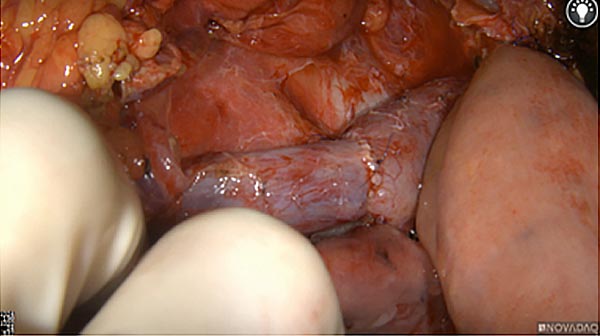

Intraoperative fluorescence imaging of the pancreas part that contains tumor

The tumor area light up fluorescently and so does a lymph node (LN; red circle) that is located on top of the tumor area. We can also see some lymphatic ducts (green circle).

After removal of the pancreas tumor fluorescence imaging was performed to check that there was no residual fluorescence left in the wound bed. A little bit of background fluorescence was found in the intestine.